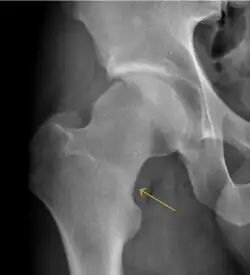

Synovial chondromatosis can be confidently diagnosed by X-ray when calcified cartilaginous chondromas are seen. However, other synovial proliferative processes, such as pigmented villonodular synovitis, require MRI for accurate diagnosis, although noncalcified synovitis can be suspected in radiographs by indirect signs, such as soft tissue swelling and/or erosions in the femoral head, femoral neck, or acetabulum (Figure 7).[1]

Figure 7:

-

Axial CT image of pigmented villonodular synovitis eroding the posterior cortex of the femoral neck.[1] -

Sagittal T2* gradient echo image showing a posterior soft tissue mass with hypointense areas secondary to hemosiderin deposition.[1] -

X-ray of synovial chondromatosis.[1] -

CT of synovial chondromatosis.[1]

In synovial proliferative disorders, MRI demonstrates synovial hypertrophy. In the case of PVNS, characteristic foci of low signal intensity related to hemosiderin deposition are better seen on gradient echo T2* images (Figure 7). In the case of synovial osteochondromatosis, the synovial hypertrophy is accompanied by intermediate signal cartilaginous loose bodies and/or low signal calcified loose bodies.[1]